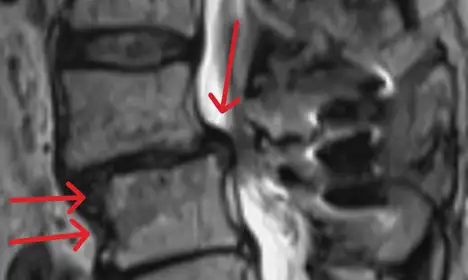

MRI scan showing spinal discs with red arrows pointing to areas of interest.

Spinal Instability

Removal of stabilizing structures causes instability requiring fusion with screws and rods.